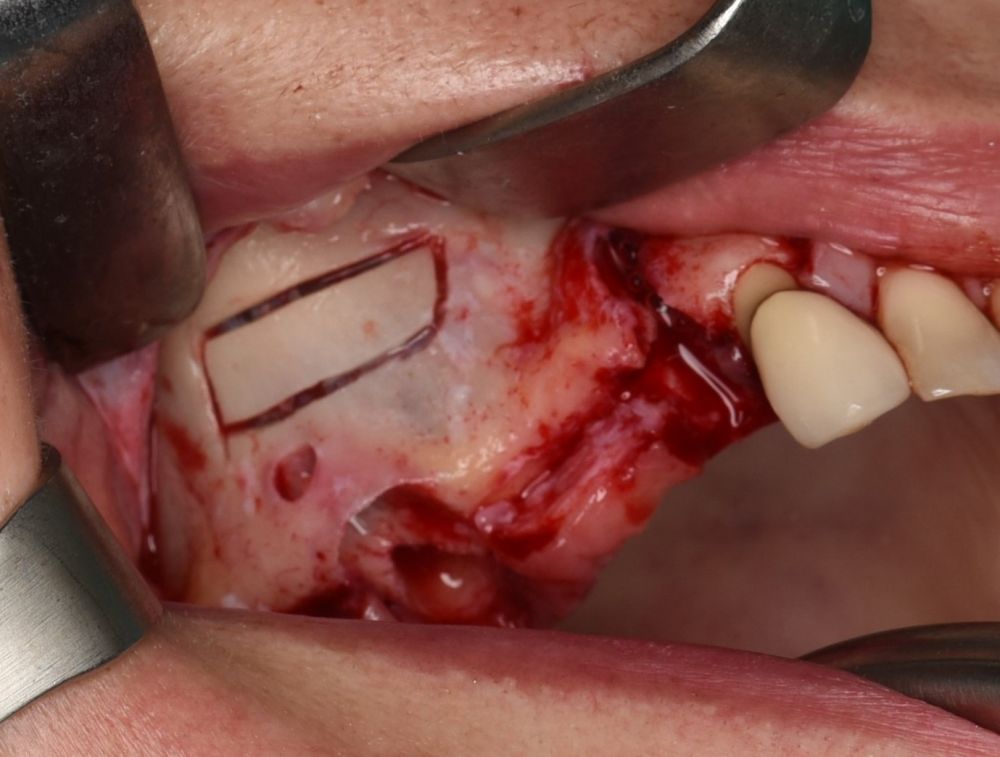

La ostectomía de acceso al seno maxilar en la pared anterior y lateral del seno maxilar de 2.5×0,8 cm se realizó con bisturí piezoeléctrico con inserto de osteotomía de diamante no dentado y abundante irrigación con suero salino (Figura 6). A continuación, se despegó la cortical y se sumergió en suero fisiológico hasta el final de la intervención (Figura 7). Se procedió a incidir la mucosa de Schneider en la zona más superior de la ventana, de mesial a distal en toda la anchura de la ostectomía, hasta penetrar en la luz del pseudoquiste (Figuras 8 y 9). Se realizó el aspirado del contenido del pseudoquiste y el epitelio del pseudoquiste se retiró cuidadosamente con una cucharilla de legrado y curetas de elevación (Figuras 10 y 11). Posteriormente, se desinfectó la cavidad con povidona yodada e irrigación con abundante suero salino. Una vez eliminado el pseudoquiste se procedió al despegamiento de la membrana de Schneider según la técnica habitual de elevación de seno maxilar abierta (Figura 12). Tras comprobar un correcto despegamiento de la membrana de Schneider se realizaron dos perforaciones con bisturí piezoeléctrico e inserto de bola de 3 mm craneales al límite superior de la ostectomía inicial (Figura 13). Se suturó la mucosa de Schneider a estas perforaciones mediante puntos simples con sutura reabsorbible 4/0 (Novosyn quick®) (Figura 14). Se colocó en el interior de la cavidad, en la zona superior, una membrana reabsorbible de colágeno (Geitlisch Bio-Guide®) que se dejó sobresalir de la cavidad hacia el exterior 1 cm (Figura 15). Se procedió al relleno de la cavidad con xenoinjerto (Geitlisch Bio-Oss® de gránulo grueso 1-2 mm) (Figura 16). La tapa de cortical que se había extraído tras la ostectomía se reposicionó y se cubrió con la membrana de colágeno que se había dejado expuesta en la zona superior (Figuras 17 y 18). Finalmente, se reposicionó el colgajo y se suturó con sutura de nylon 5/0 monofilamento no absorbible (Figura 19).